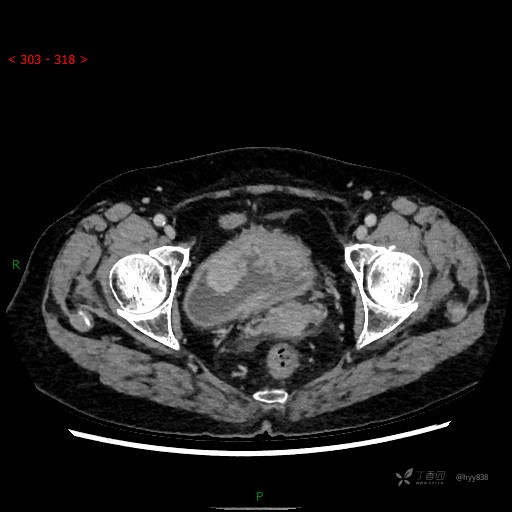

膀胱少见肿瘤,欢迎挑战---结果公布~

华夏览雄 达人已点赞患者性别:女

患者年龄:73岁

主诉:肉眼血尿3周

简要病史:患者诉3周前无明显诱因开始出现肉眼血尿,发作时尿液呈鲜红色,为全程血尿,无明显血凝块;伴小腹胀痛,无尿频、尿急、尿痛;无寒战、发热;无恶心、呕吐,就诊于当地医院行输液治疗后,出现不规则血凝块,进一步完善相关检查提示膀胱占位,活检提示膀胱炎性改变,现患者为进一步治疗,遂来我院,门诊以“膀胱肿物”为主诉入院。 起病以来,患者精神、饮食、睡眠稍差,大便如常,小便如上述,近期体力、重无明显变化

辅助检查:CT

临床诊断:膀胱肿瘤

膀胱CT平扫(2022.10.20)

增强(2022.11.1)